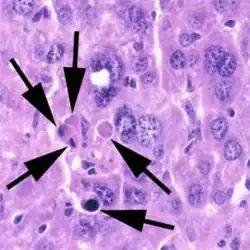

Buňka procházející apoptózou se odlišuje od běžných buněk zejména těmito rysy:

- Pyknóza chromatinu (kondenzace do kompaktních shluků),[12][13] načež proběhne karyorrhexe (tzv. internukleozomální štěpení DNA do relativně malých úseků)[14] a následný rozpad jádra (karyolýza)[9]

- Rozpad buňky na apoptotická tělíska[9]